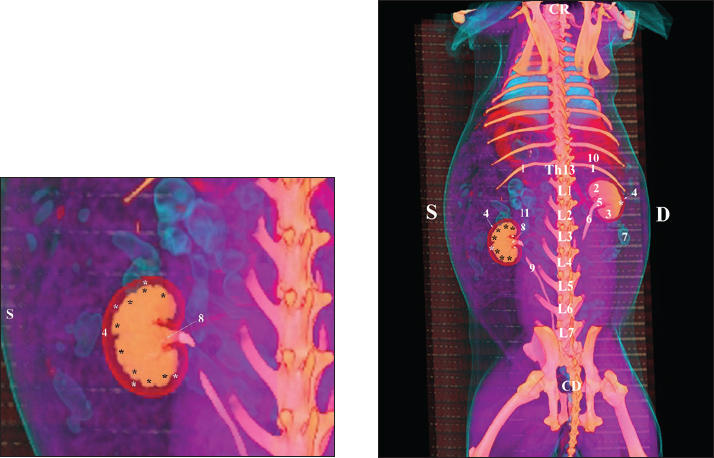

The retrospective reconstruction in the Bones and Skin 1 and Bones and Skin 3 modes provided information about the anatomical features of both kidneys, including surface relief and renal pyramids. The two kidneys were multipapillar organs with 6–8 pyramids; their tips were fused into a single crista renalis, directed toward the renal pelvis. Dorsally and ventrally, the renal pelvis became wider to form recessus renalis, аnd its terminal part continued toward the ureter. The cortex renis and medulla renis were distinct soft tissue findings, and the boundary between the capsula fibrosa and capsula adiposa was clearly defined (Figs. 20 and 21).

Fig. 20. Retrospective reconstruction of computed tomography (CT) data in Bones and Skin 1 mode in a rabbit: (1) Crista renalis; (2) left ureter; (3) right ureter; (4) recessus renalis; (*) papilla renalis; (5) XIII rib.

Fig. 21. Retrospective reconstruction of computed tomography data in Bones and Skin 3 mode in a rabbit. (1) XIII h rib; (2) extremitas cranialis; (3) extremitas caudalis; (4) capsula adiposa; (5) pelvis renalis (right kidney); (6) right ureter (pars abdominalis); (7) pars descendens of the duodenum; (8) pelvis renalis (left kidney); (9) left ureter (pars abdominalis); (10) lobus caudatus (proc. caudatus); (11) pars ascendens of the duodenum.

Retrospective reconstruction in the Angio–Right and Left mode (right and left sides) yielded information about the localization of both kidneys in the RA. The right kidney was located in the region abdominis cranialis and region abdominis media, between Th13 (L1) and L2–L3, whereas the left kidney was located between L2 (L3) and L4 (L5) (Figs. 22 and 23).

The presented information about the bilateral localization of both kidneys and the cranial position of the right kidney in relation to the left one confirmed Bensley’s (1948) thesis on the topography of these organs in rabbits. Furthermore, the retrospective reconstruction of CT data in Bones and Skin 1 and Bones and Skin 3 modes demonstrated the presence of well-formed renal papillae, which disagrees with the existing theories about the unipyramidal structure of the rabbit kidney (Bensley, 1948; Brewer, 2006; Dyce et al., 2010). The presence of well-developed capsula adiposa, capsula fibrosa, and distinctive cortex renis, medulla renis, and pelvis renalis in the Bones and Skin 3 reconstruction mode was added to the anatomical structure of rabbit kidneys (Bensley, 1948; Dyce et al., 2010).

The presented evidence on the multipapillary structure of the two rabbit kidneys differs from the theory about the primitive structure of these organs (Dimitrov and Chaprazov, 2012a,b). On the other hand, the established bean-like shape and the sharply demarcated boundary between the cortex and medulla in the Bones and Skin 3 reconstruction correspond to the existing data on the structure of these organs (Dimitrov and Chaprazov, 2012a,b).

The eight papillae, the presence of a distinct crista renalis, the topographic location of the right kidney between Th13 (L1) and L2–L3, and the left kidney between L2 (L3) and L4 (L5) expand the theory (Barone, 2020) about the pyramidal structure of these organs, as well as their topographic location in the abdominal cavity. The obtained data are intravital and largely influenced by the inspiration and expiration phases.

The eight papillae and smooth surfaces of both kidneys are consistent with published data describing the smooth and multipyramidal nature of the rabbit kidney (Stamatova-Yovcheva et al., 2022).